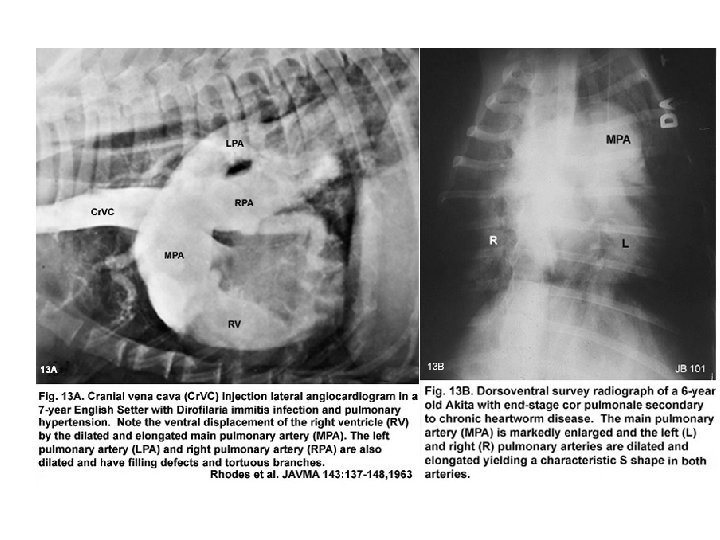

CANINE HEARTWORM DISEASE • PREDOMINANT PATHOLOGY: DAMAGE TO THE PULMONARY ARTERY FROM ADULT HEARTWORMS – Endothelial damage and sloughing – Inflammation (leukocytes, platelets) • Risk of thromboemboli – Pulmonary hypertension – Disruption of vascular integrity • Thickened, fibrosed • RIGHT VENTRICULAR HYPERTROPHY AND RIGHT-SIDED HEART FAILURE – The right ventricle compensates by dilating and increasing muscle thickness – Ultimately, there is decompensation and heart failure

• The yellow arrows point to the tortuous and severely enlarged pulmonary arteries. • There is a mild increase in the size of the right atrium. • The pulmonary parenchyma also has a slight interstitial pattern.